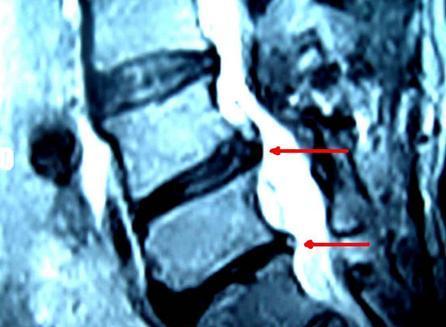

腰椎間盤突出癥引發(fā)坐骨神經(jīng)痛怎么辦?怎樣簡(jiǎn)單有效改善?腰椎間盤突出癥是以腰、臀、腿痛,麻木,乏力,感覺減退為特征的常見病。椎間盤是脊柱每一骨節(jié)之間的震蕩緩沖體。如果椎間盤突出在原來(lái)位置之外,就會(huì)侵犯、刺激、壓迫附近的脊髓、神經(jīng)根、交感神經(jīng)而引起疼痛。